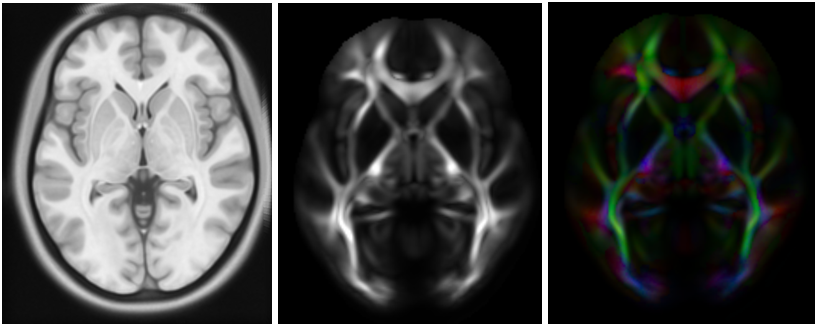

The neuroscience community has made important advances in brain imaging techniques in recent years. Improved precision of Magnetic Resonance Imaging (MRI) that illuminates white matter pathways, DT-MRI, allows medical professionals to non-invasively identify anatomy which requires attention from a surgical or therapeutic standpoint.2 Utilizing advanced registration techniques, high-resolution templates can be created for cohort groups of subjects, such as healthy or individuals affected by a mental condition which causes differences in anatomical sizes for certain regions of the brain.3 Similarity metrics can be used to compare anatomical structures between a set of cohort templates and a DT-MRI scan of unseen subjects. The template creation strategy and analytical tools is a framework which will enable the pre-clinical DT-MRI studies for understanding and treating brain disorders.4

The image processing pipeline of DT-MRI utilizes a T1 weighted MRI image as a registration target for a set of diffusion weighted MRI images obtained by varying the magnetic field direction. The notion behind this novel imaging technique comes from the observation that water molecules will diffuse along the direction of the magnetic field when inside of a fiber traveling in the same direction, producing a high signal. Water molecules will not diffuse outside of a fiber, so a fiber which is perpendicular to the incoming magnetic field will yield a signal of zero. A diffusion tensor is then computed for each voxel that can describe local water diffusion. Sophisticated image pre-processing steps are often required for DT-MRI such as denoising and accounting for other device specific distortions. Each diffusion weighted image is registered to the T1 image, and additional images can be derived from the co-located data such as Fractional Anisotropy (FA), and Directionally Encoded Color (DEC) maps, as shown in Figure 1. The template displayed below was obtained through the Human Connectome Project open dataset and was formed using scans of 842 subjects, 372 of which were male and 470 were female and were between 20-40 years old.5 The FA image shows the major white matter pathways in the brain and can be used along with other derived images such as the DEC map to create other useful data visualizations such as fiber tractography reconstruction. Tractography is an approach to generate 3D models of anatomy out of the major fiber pathways discovered through DT-MRI and can be visualized in a graphics rendering engine. Using a DT-MRI template and derived images from Figure 1, full brain fiber tractography can be generated. Furthermore, fibers emerging from and terminating into specific brain regions, such as the amygdala, can be selected for detailed analysis shown in Figure 2.

Figure 1 Axial representation of the DT MRI processing pipeline. (a) A T1 weighted image is used as a reference image, (b) FA is computed using multiple diffusion weighted images, and (c) a DEC map is created, where colors indicate fiber orientation.